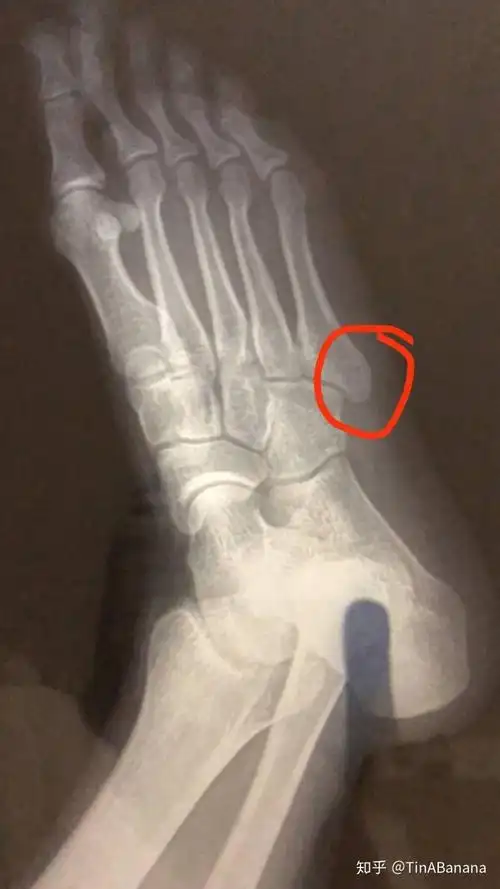

2020右脚骨折恢复记录

右脚第五跖骨基底部骨折